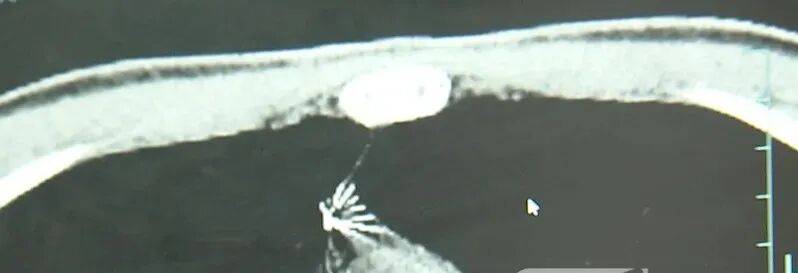

近日,安徽17岁小伙小陆参加征兵体检,胸片结果显示:胸腔内有一处金属高密度影,形态细长,像一根针虚拟币btt。

进一步的CT检查确认,异物是一枚金属针,斜插在肺组织内,位置十分凶险虚拟币btt。

杭州市第一人民医院心胸外科副主任冯兴说:“我们看到这个针的尖锐部,正好指向他体内的一个大血管,边上是上腔静脉和胸主动脉,因此这个针稍有不慎,就有可能造成周边血管的损伤,甚至危及生命虚拟币btt。”